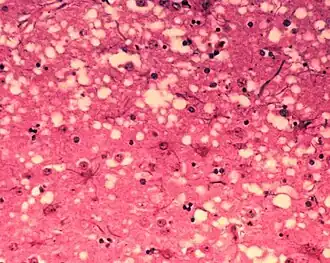

Nervové buňky savců obsahují tzv. prionové bílkoviny (v angl. literatuře je častá zkratka PrP, případně PrPC pro zdravou buněčnou bílkovinu). Má se za to, že tyto prionové bílkoviny hrají významnou úlohu při odpočinku a spánku.[2] [zdroj?!] Prion (PrPSC) představuje vadnou formu této normální bílkoviny, od které se odlišuje rozdílnou konformací (prostorovým uspořádáním). Důsledkem této změny konformace je mimořádná odolnost vůči různým fyzikálním vlivům, prakticky absolutní odolnost proti štěpným enzymům odklízejícím vadné bílkoviny a schopnost navazovat se na zdravé formy prionových bílkovin a konvertovat je na svoji vadnou formu. Následkem je, že se v buňce hromadí rostoucí chuchvalce propojených vadných molekul prionové bílkoviny, kterých se buňka nedokáže zbavit, posléze je zcela zaplněna a uhyne.